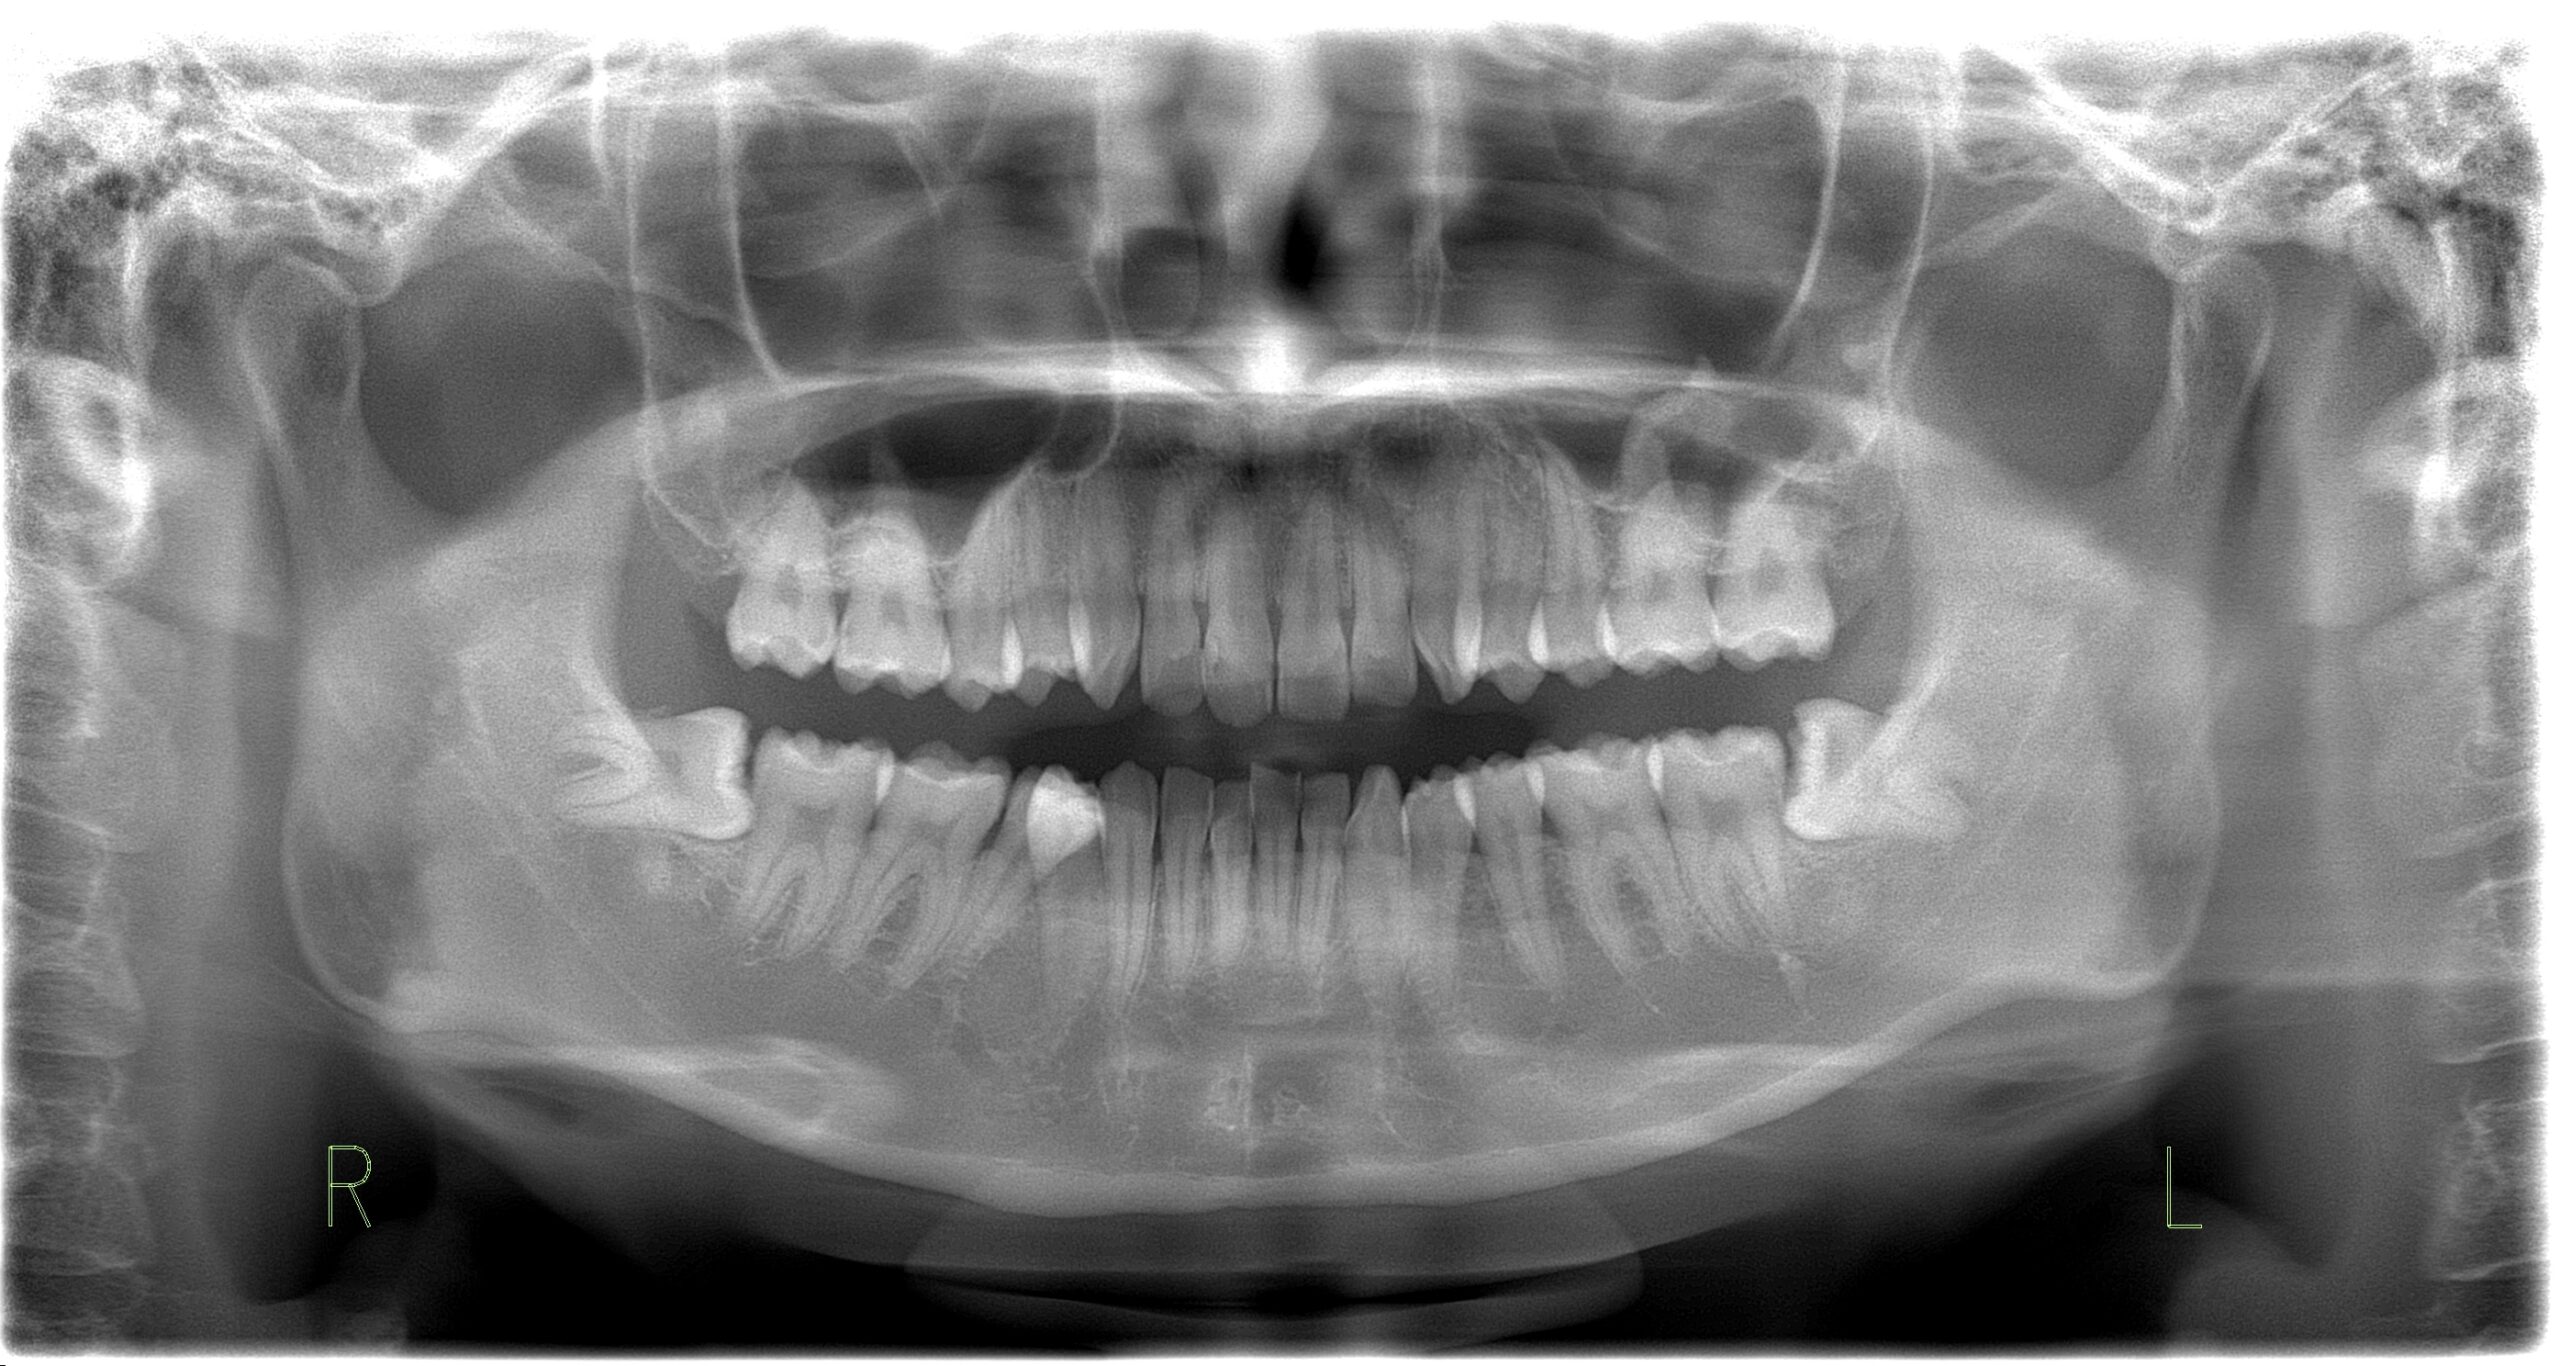

親知らずは口の一番奥に生える大きな歯です。ほとんどの人の親知らずは、17 歳から 21 歳の間に皮膚から生えてきます。親知らずがまったく生えていない人もいます。

場合によっては、親知らずが正しい位置に移動するための十分なスペースが口内にない場合があります。歯肉を斜めに突き破ったり、部分的にしか突き抜けなかったりすることがあります。これが発生すると、 埋伏親知らずと呼ばれ、痛みや感染症などの問題を引き起こす可能性があります。

親知らずが成人期に生えてくると、口の中の他の歯はすでに所定の位置に定着します。口には、4 本の大きな歯が生えるのに十分なスペースがないことがよくあります。

歯が歯茎の途中までしか生えていない場合、食べ物が歯と歯茎の間に挟まりやすくなります。また、これらの歯を清潔に保つことが難しくなり、感染症や虫歯につながる可能性があります。

ただし、親知らずが歯茎を完全に突き抜けて生えている場合でも、問題が発生する可能性があります。斜めに生えていると、口の中や歯茎をこすってしまう可能性があります。他の歯を押して痛みを引き起こす場合があります。

青年期や成人初期に定期的に歯科医院を受診すれば、歯科医は親知らずの生え方を常に監視し、問題がないかどうかを特定できるはずです。